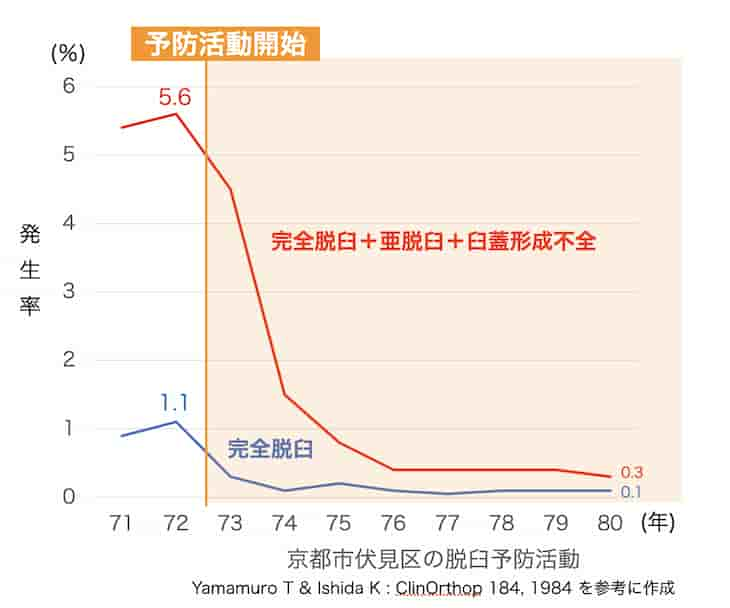

発生率

1才以降に発見される脱臼が急増している

15%という遅診断率は諸外国と比べても桁違いに高い数字(英国 0.03%、ノルウェー 0.3%)です。健診を受けても発見されず、歩行開始後に診断されて、牽引・手術で治療されている児が毎年100人もいるという事実は、今の日本のやり方に問題があることを示しています。

日本の問題点

欧米では出生直後から何回も脱臼をチェックする健診があり、超音波検査も広く普及しているので、歩き始めるまで見逃されることはほとんどありません。日本では3〜4ヶ月健診が早期発見のほぼ唯一の機会となっています。また、早期発見には必須といえる超音波検査を行っている医師が非常に少ないことも影響しています。これらの要因によって、実に脱臼の6人に1人が歩行開始後に発見されるという状況になっています。